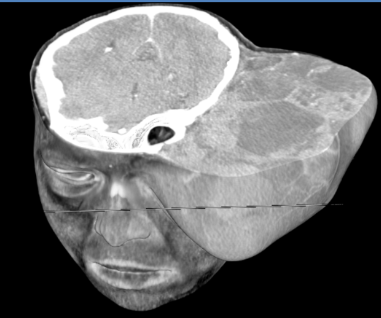

- Large, expansile mass on the left hemiface causing distortion of facial structures, including the ipsilateral eye and ear. The lesion shows two necrotic regions: one anteriorly and the other laterally.

- Soft tissue density mass, involving the superficial layers of the left hemiface, apparently originating from the cutaneous and subcutaneous tissues.

- The mass is composed of nodular material with heterogeneous attenuation. The nodules have hyperdense contours and predominantly hypodense internal contents with heterogeneous enhancement.

- Irregularity in the cranial skull with thinning and remodeling.

- There was no intracranial extension.